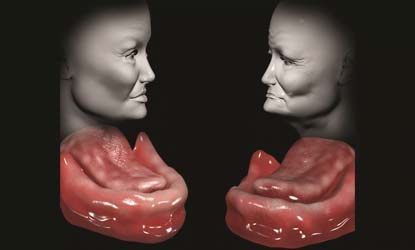

Veido kontūrų išlaikymas

Dantų implantai atlieka palaikomąją žandikaulio kaulo funkciją, todėl implantus įsriegus iškart po danties rovimo, minkštųjų ir kietųjų audinių, veido kontūrų būklė lieka tapati.

Jei išrautų dantų nepakeisime dantų implantais, laikui bėgant keičiasi veido kontūrai: lūpos sukrenta į burnos ertmę, skruostikauliai praranda savo formą, smakras tampa smailesnis o nosis labiau atsikišus. Todėl žmogus, neturintis dantų, nors ir yra vidutinio amžiaus, atrodo kaip senyvo amžiaus žmogus.